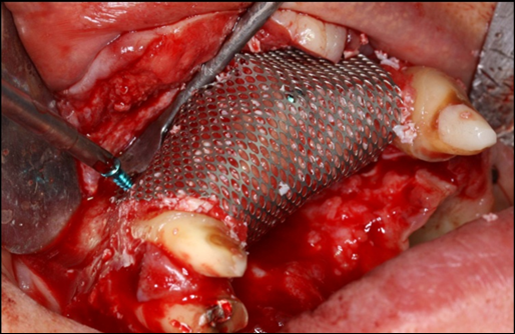

The surgical procedure was done under intravenous sedation using Fentanyl and Versed. Local anesthetic was used and a supra-crestal horizontal incision made on the palatal aspect of the anterior maxilla. A mucoperiosteal flaps were elevated, exposing a severely resorbed ridge of the pre-maxilla (Figure 2). Decortication was conducted with a round carbide bur in order to perforated the cortical aspect of the bone and expose the cancellous bone, to increase vascularity to the recipient site. Three screws were fixed parallel to the adjacent teeth, serving as “tent pole”. The screws had 14 mm length and approximately 6-8 mm of the tenting screws were exposed to the oral cavity (Figure 3). An absorbable collagen sponge (ACS) carrier/matrix was embedded with 12 mg of rhBMP-2 at 1.5 mg/mL (Infuse® Medtronic Sofamor Danek, Memphis, TN, USA) and allowed to absorb for approximately 20 min. The rhBMP-2/ACS was cut into strips, half of the strips were added to the natural bone mineral component derived from bovine bone (Geistlich Bio-Oss® granules small - 0.25 to 1 mm, Geistlich Pharma, Germany). Initially, some strips of rhBMP-2/ACS were placed over the buccal aspect of the residual alveolar ridge of the pre-maxilla, followed by strips mixed with bovine bone (Figure 4). The three screws were fully covered by rhBMP-2/ACS strips. Finally, a titanium mesh was adapted over the entire rhBMP-2/ACS graft and fixed with 2 monocortical screws, one on the buccal aspect and one on the palatal aspect of the ridge, respecting a 2 mm distance from the mesh to the adjacent teeth (Figure 5). Extensive undermining incision was conducted on the apical aspect of the buccal flap in order to achieve primary closure.

Figure 5.Perspective view of the pre-maxilla showing a titanium mesh adapted over the entire rhBMP-2/ACS graft and fixed with 2monocortical screws, one on thebuccalaspect and oneon the palatal aspect of the ridge, respecting a 2 mm distance form the mesh to the adjacent teeth